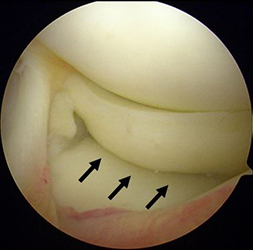

半月は、膝関節の大腿骨と脛骨の間にあるC型をした軟骨様の板で内側・外側にそれぞれがあり、クッションとスタビライザーの役割をはたしています。半月板損傷は、スポーツ外傷や加齢性の変化などにより、幅広い年齢層に生じます。症状は、引っかかり感や関節が曲がらない・伸びないなどの関節可動域制限、しゃがんだ際などの痛みであり、痛みがひどい場合には、夜間寝返りで目が覚めることもあります。半月板は損傷すると治りにくい組織です。保存的治療で症状改善が得られない場合、関節鏡視下の半月板部分切除術や縫合術をお勧めします。

関節鏡視下半月板部分切除術・縫合術

前方に逸脱した外側半月板を整復し縫合した。